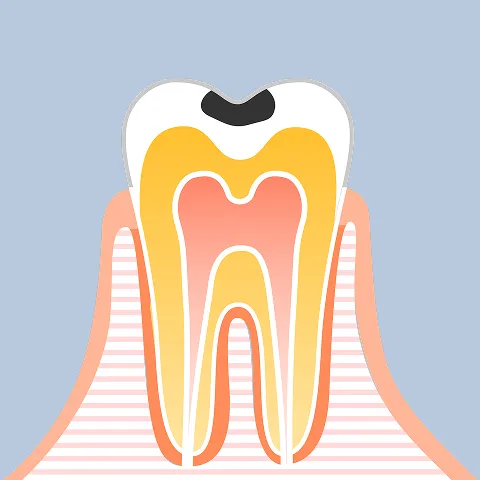

- C1

エナメル質の溶解

(要観察・初期治療) - C2

象牙質の汚染

(修復治療) - C3

歯髄炎

(神経への感染) - C4

歯質崩壊・残根

(保存の限界・

抜歯の危機)

「C3・C4」は、歯を失う直前の危険信号。 未来を変えるのは、感染源を断つ「精密根管治療」です。